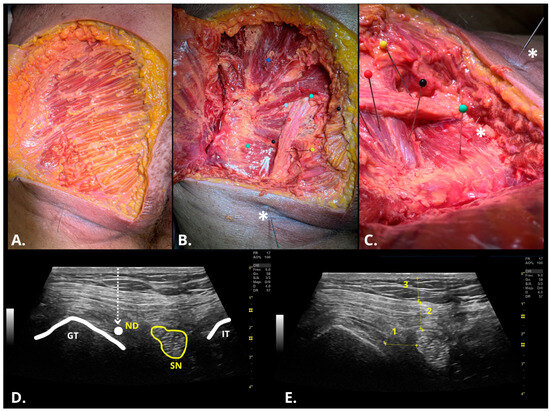

2.4. Ultrasonographic Assessment of DDN Procedure

2.5. Disecction Assessment of DDN Procedure